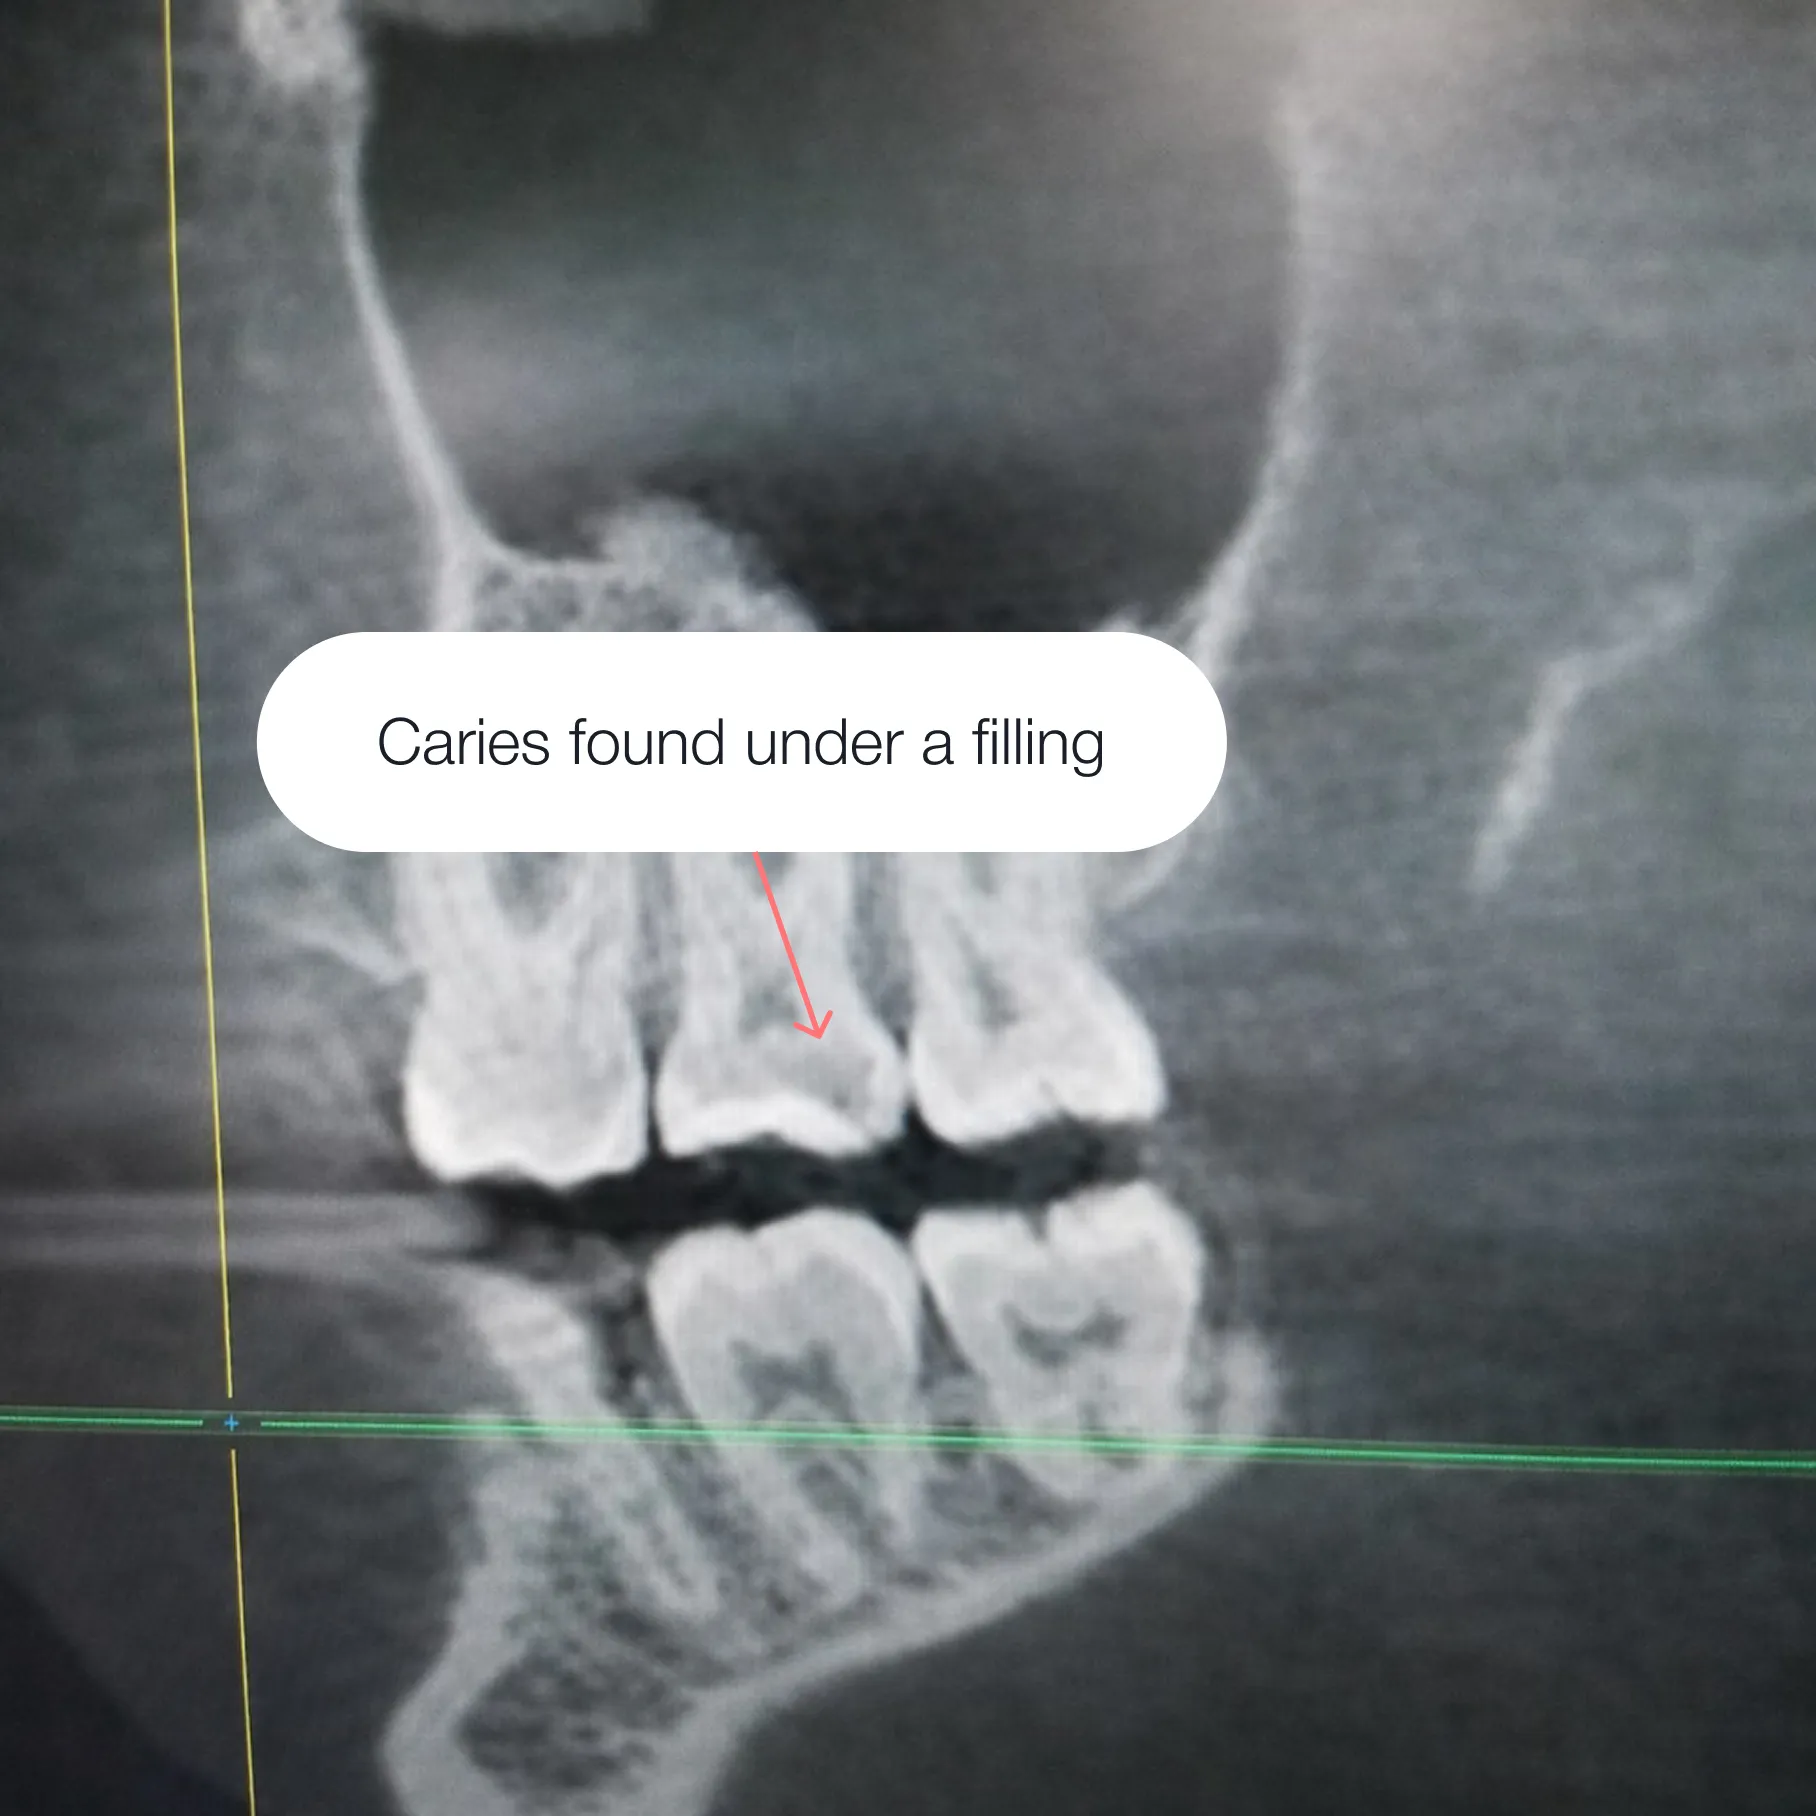

Caries spread from the inside, and if treatment is delayed, the damage will deepen. This can lead to:

Early intervention allows the tooth to be fully preserved and prevents complications.